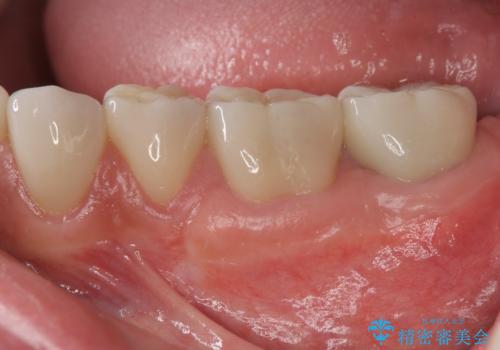

老朽化した前歯のセラミック治療やりかえ

- 52万円(仮歯・ファイバーコア・ジルコニアクラウン×4)費用は治療当時の料金となります

クラウン治療は経年的に歯ぐきの位置が変わり汚れが溜まってしまったり、見た目が悪くなるなどの問題が出てくることがあります。

現在の歯ぐきの位置できっちりと仕上げることで見た目の改善が達成されました。